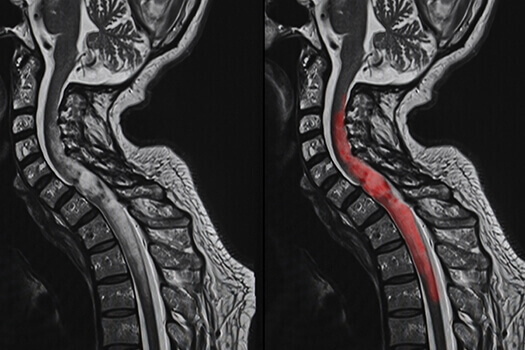

脊髓髓内肿瘤,如下图所示,是指硬膜内肿瘤的一个亚组脊髓的源于脊髓内细胞的肿瘤,与邻近结构如神经根或脑膜相对。它们比脑肿瘤少得多,被认为占中枢神经系统全部固有肿瘤的...

髓内脊髓肿瘤(IMSCTs),如下图所示,是指硬膜内 脊髓肿瘤 的一个亚群,由脊髓内的细胞产生,与相邻结构如神经根或脑膜相对。它们比脑瘤少见得多,据认为占中枢神经系统全部固有肿...

什么是脊髓髓内肿瘤?脊髓髓内肿瘤约占椎管内肿痛的15%-90%,以发生于颈、胸段椎管者多见,髓内肿瘤中,主要为各类型的胶质瘤,少数为上皮样囊皮祥囊肿、血管网状细胞瘤和脂肪瘤...